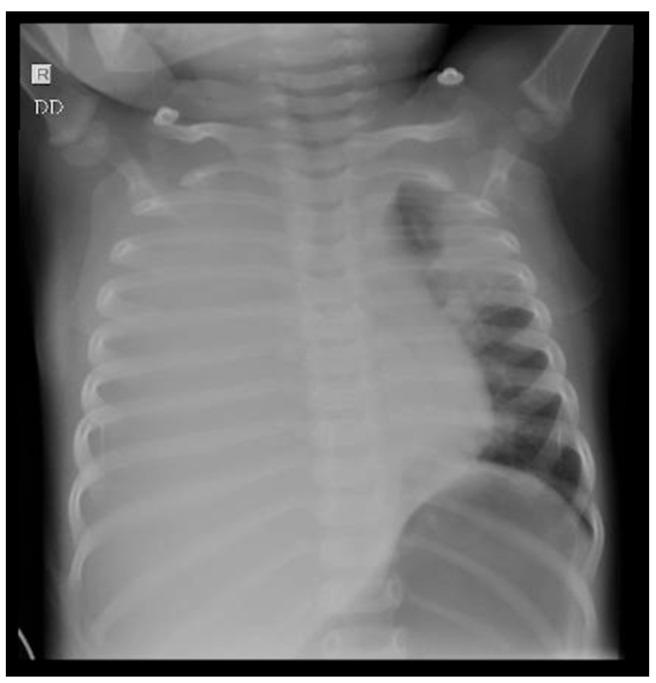

Hemophagocytic lymphohistiocytosis (HLH) is a rare, and potentially fatal, syndrome, characterized by immune system dysregulation, with excessive activation of the macrophages and cytotoxic T cells. It can be classified into primary (genetic) and secondary (acquired) forms. HLH presents with fever, hepatosplenomegaly, cytopenia, and hyperferritinemia, with involvement of various organs. The initial symptoms of HLH are non-specific, but as, if untreated, it can progress rapidly to multiorgan failure, timely diagnosis is essential. We present here two cases of HLH in infants that illustrate the importance of early diagnosis and appropriate treatment, along with a short review of HLH.

噬血细胞性淋巴组织细胞增生症(HLH)是一种罕见且可能致命的综合征,其特征为免疫系统失调,巨噬细胞和细胞毒性T细胞过度活化。它可分为原发性(遗传性)和继发性(获得性)形式。HLH表现为发热、肝脾肿大、血细胞减少和高铁蛋白血症,并累及多个器官。HLH的初始症状不具特异性,但如果不治疗,它可迅速进展为多器官功能衰竭,因此及时诊断至关重要。我们在此介绍两例婴儿HLH病例,阐述早期诊断和恰当治疗的重要性,并对HLH进行简要综述。